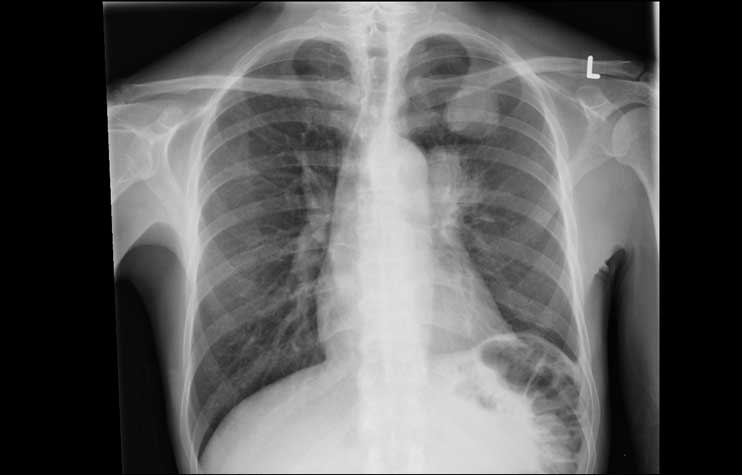

Handelt es sich bei diesen Röntgenbilder von der Lunge unseres Hundes